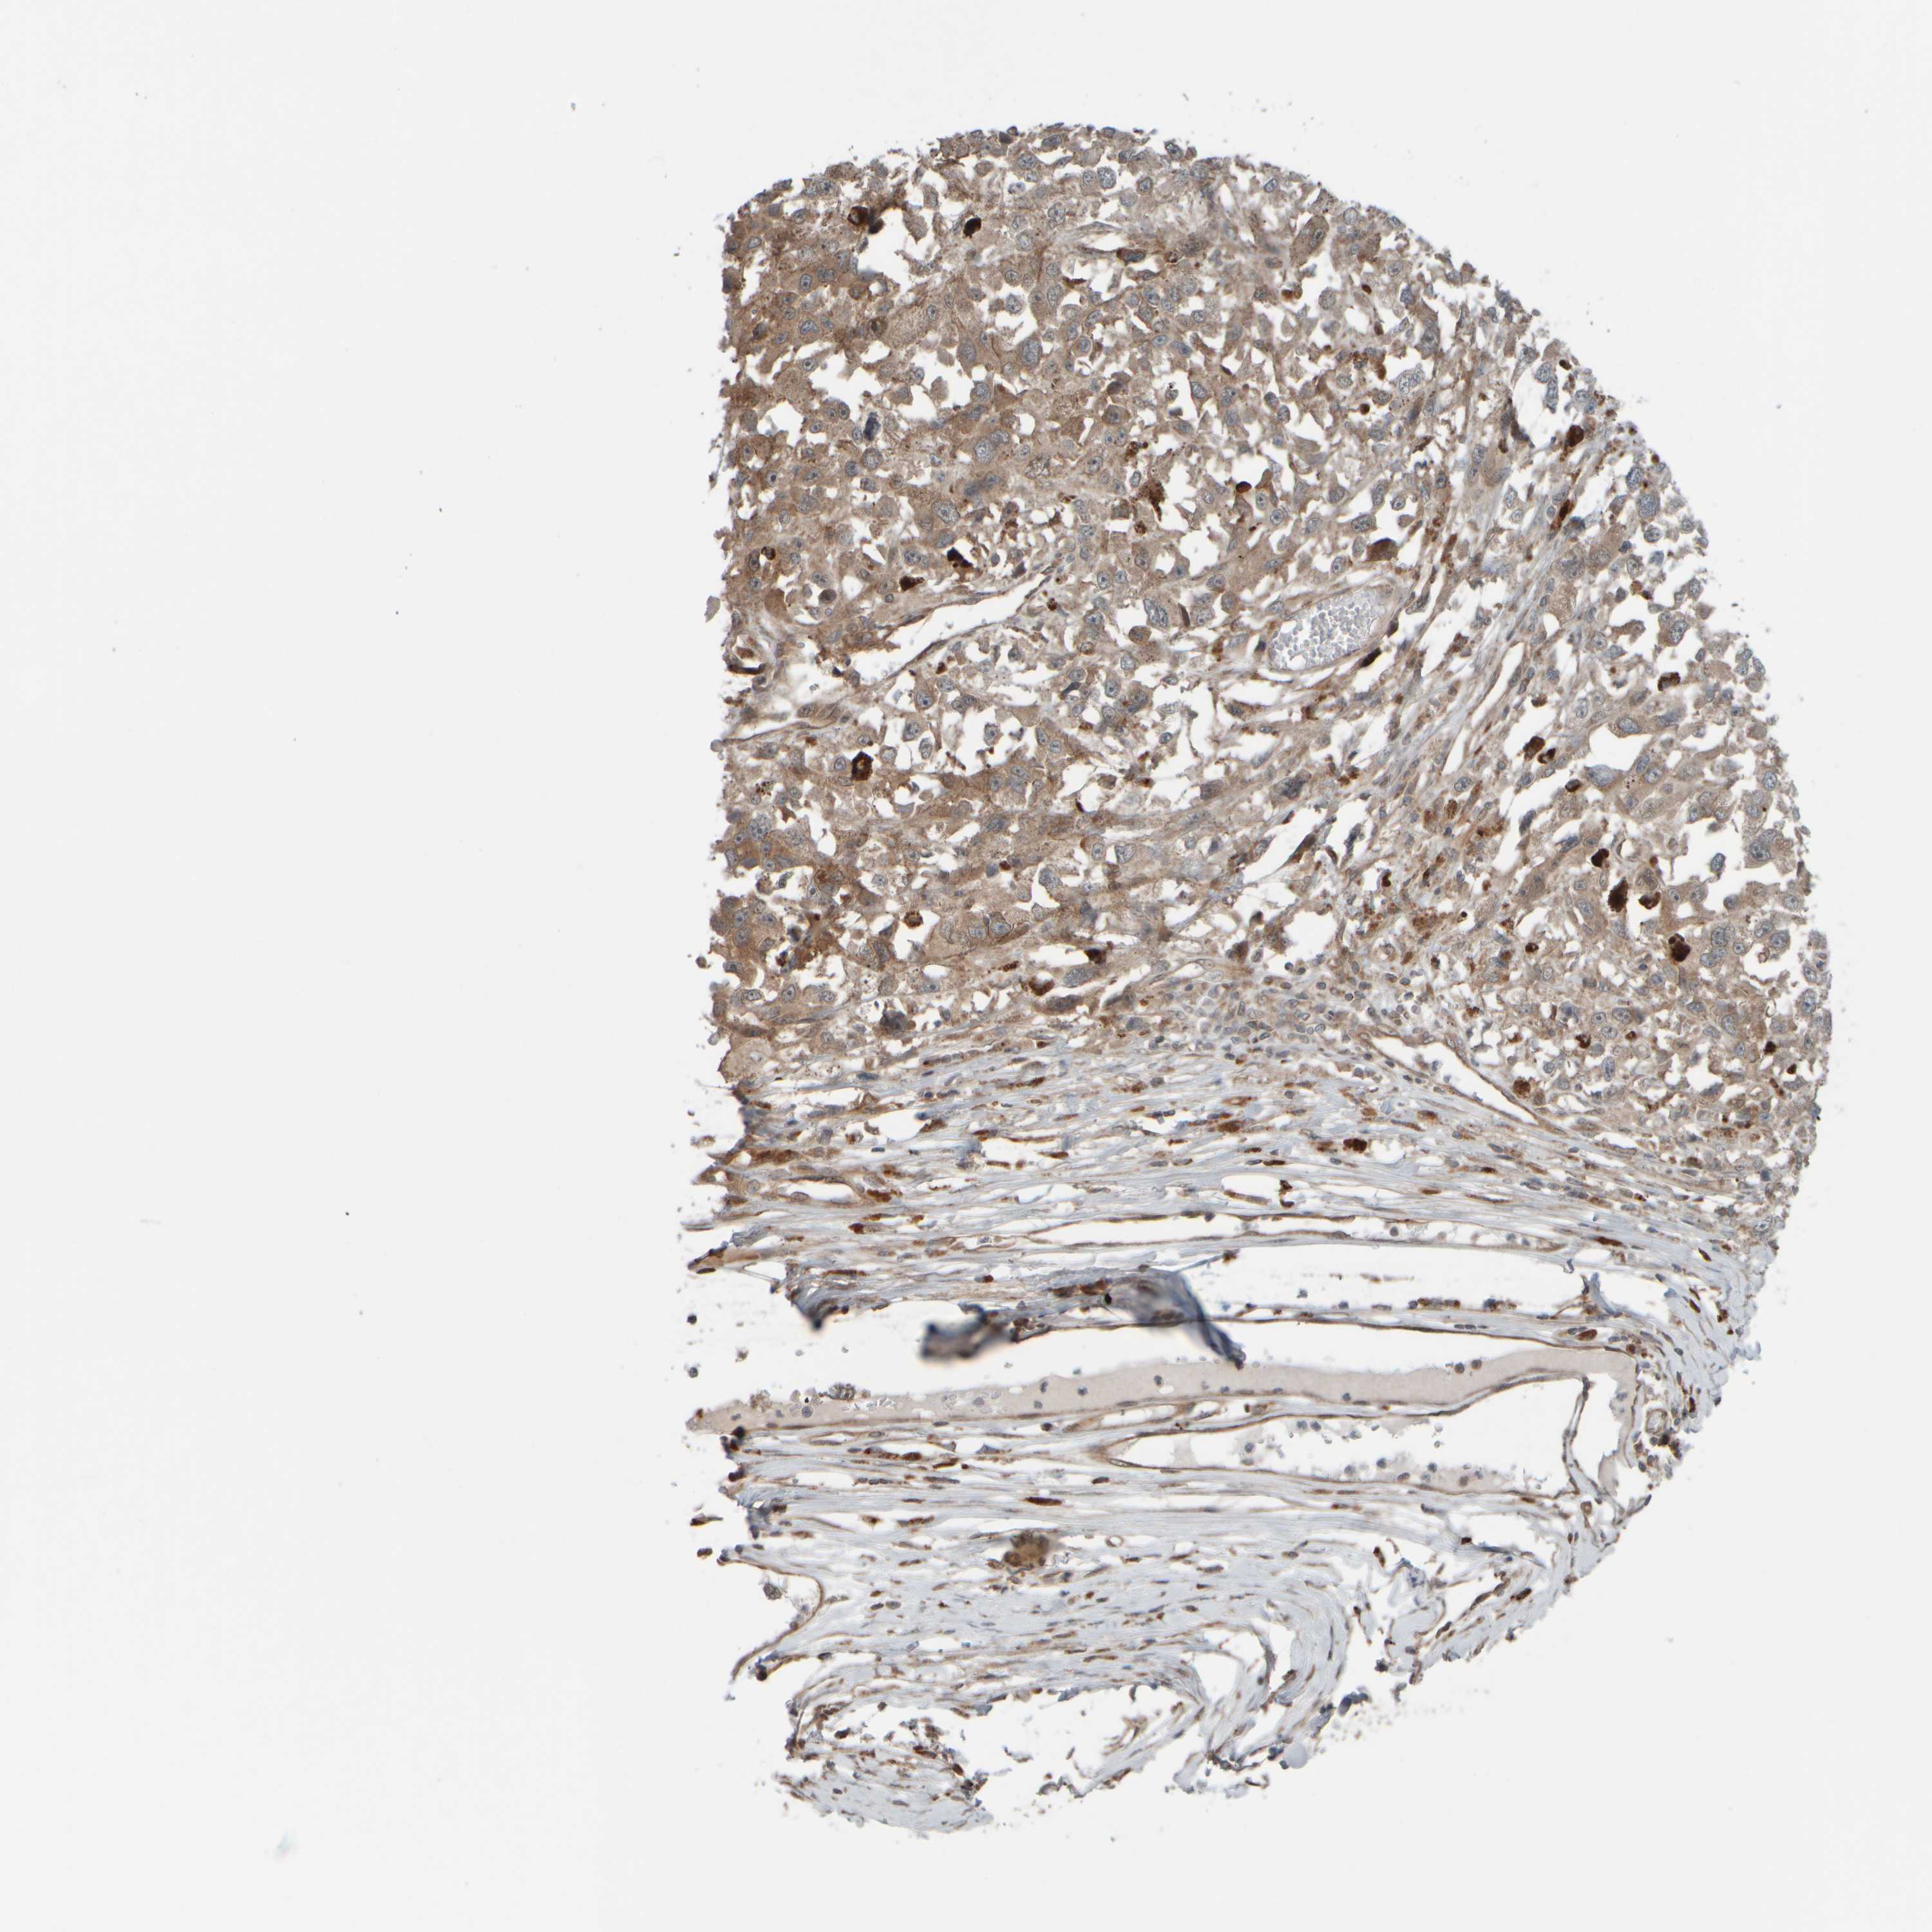

MELANOMA - Protein expressioni

A mouse-over function shows sample information and annotation data. Click on an image to view it in a full screen mode. Samples can be filtered based on level of antibody staining by selecting one or several of the following categories: high, medium, low and not detected. The assay and annotation is described here.

Note that samples used for immunohistochemistry by the Human Protein Atlas do not correspond to samples in the TCGA dataset.

Antibody stainingi

Antibody staining in the annotated cell types in the current human tissue is reported as not detected, low, medium, or high, based on conventional immunohistochemistry profiling in selected tissues. This score is based on the combination of the staining intensity and fraction of stained cells.

Each image is clickable and will lead to virtual microscopy that enables deeper exploration of all samples and also displays staining intensity scores, fraction scores and subcellular localization as well as patient and tissue information for each sample.

Antibody HPA020999

Antibody HPA023995

Staining

High

Medium

Low

Not detected

Intensity

Strong

Moderate

Weak

Negative

Quantity

>75%

75%-25%

<25%

None

Location

Nuclear

Cytoplasmic/membranous

Cytoplasmic/membranous,nuclear

Malignant melanoma, NOS

Malignant melanoma, Metastatic site